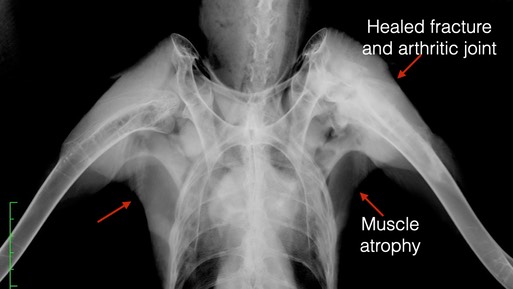

And finally, Golden Eagle 21-004 was admitted with a humerus fracture in the left wing that was two or three weeks old. The fracture was healed, but the eagle had little use of the left shoulder. If you look at the radiograph below you will notice there is significantly less muscle on the left when compared to the right side. The eagle was humanely euthanized.